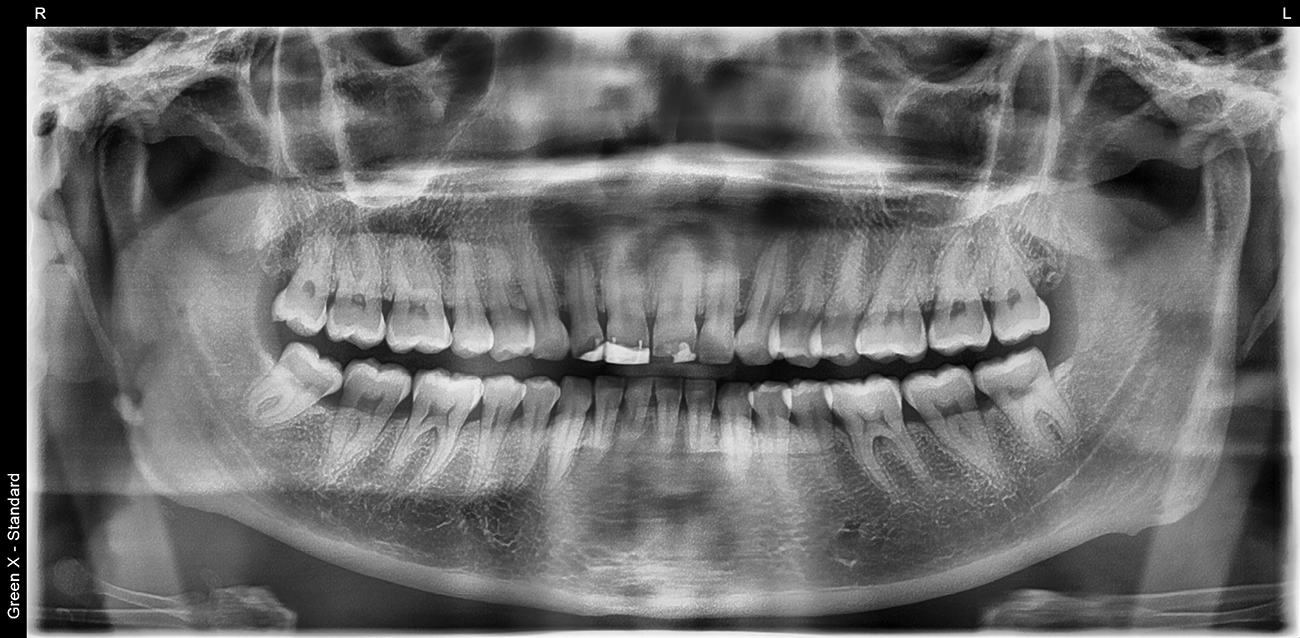

Die ursprüngliche Planung sah vor, den alten Kunststoff und den Metallstift im Schneidezahnbereich behutsam zu entfernen, ohne dabei die gesunden Zähne zu beeinträchtigen. Beim Entfernen ging jedoch vor allem an Zahn 12 und 11 unerwartet viel Zahnsubstanz verloren. Dementsprechend musste die Behandlungsmethode angepasst werden. Ein bestmögliches Ergebnis versprach nach einer Zahnaufhellung die Versorgung der oberen Schneidezähne mit 4 Zirkoniumdioxidkronen.

Um die Zähne 21 und 22 so vital wie möglich zu erhalten, wurden sie rundum lediglich um ca. 1,5 mm reduziert. Bei den Zähnen 11 und 12 war dies vor allem inzisal nicht möglich, da sie nach der Entfernung des Metallstiftes und des Kunststoffes stark reduziert waren, jedoch nicht so stark, dass eine Wurzelbehandlung notwendig gewesen wäre. Die Zähne wurden anschließend mit neuen Kunststoffaufbauten versorgt und für monolithische Zirkoniumdioxidkronen präpariert. Während der provisorischen Versorgung wurden die Zähne regelmäßig kontrolliert, um den Erfolg der Restauration und das Ausbleiben von Komplikationen sicherzustellen (Abb. 53 bis 56).